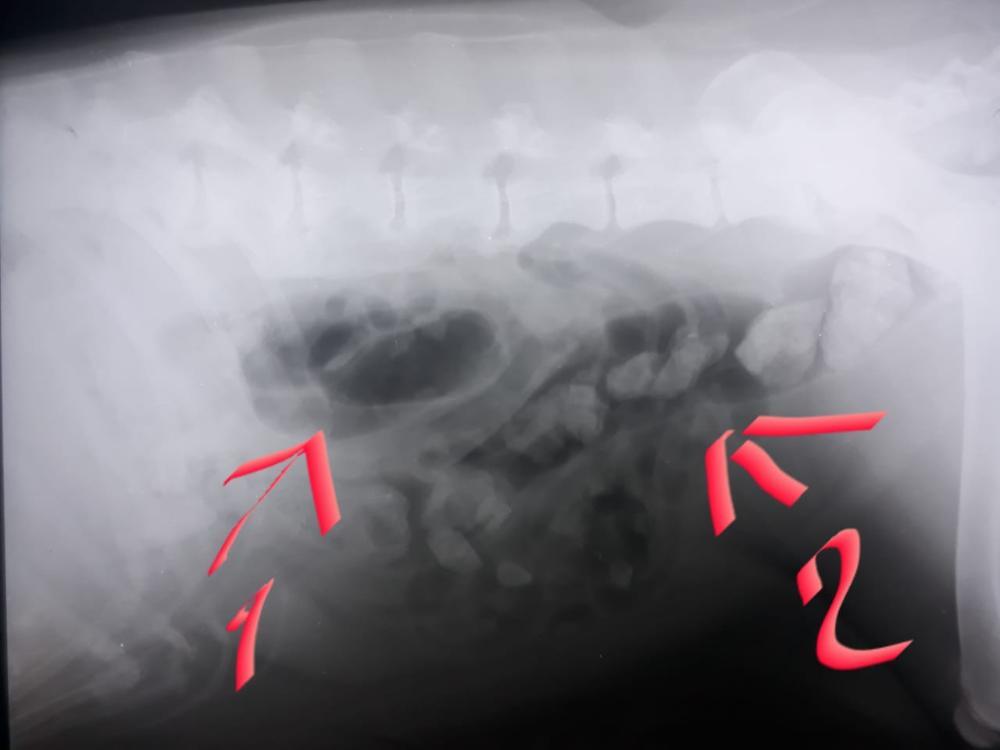

Утром к открытию рванули в ветклинику. Вет ее внимательно осмотрела, сказала что на отравление не похоже, сделала рентген брюшной полости и гортани на предмет инородки, инородку не нашла, зато нашла сломанные уже сросшиеся ребра. Вколола противорвотное и отправила нас до вечера домой. Аппетит и стул не изменился ттттт, только не веселая она была, видно что намаялась. После работы повезу еще раз. Снимки и выписки заберу вечером.

1.jpeg.6c014be23d50e49421e812d0f0620ad4.jpeg

2.jpeg.bd53a033fd36de97a00bad1e8f2b0c7a.jpeg

На снимке цифра 1 пятно – это вздутый кишечник, а цифра 2 она спросила "она у вас камни не ест?", нет, камни не ест, прибавила ей порцию хрящей на прошлой неделе, какахи стали суховатые, она выдавала их маленькими порциями, не нравится, верну костно-хрящевое как было.